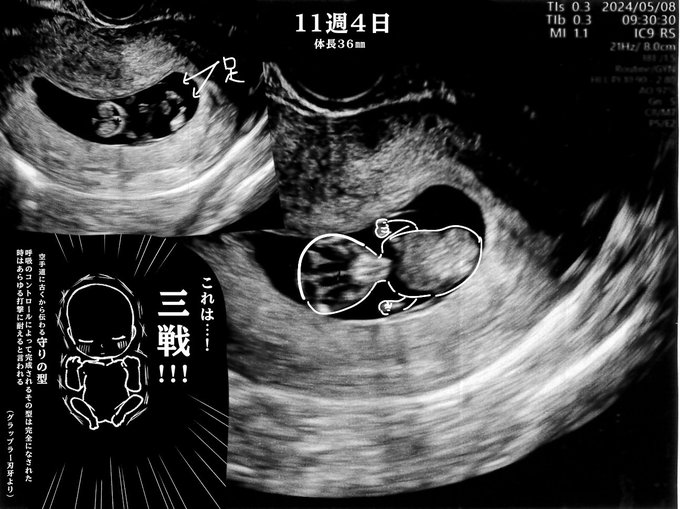

お久しぶりのポストです。

こちらで報告が遅れましたが、妊娠しました。

多嚢胞性卵巣症と診断され(1枚目)

治療を経て卵子が育つようになり(2枚目)

タイミングで授かりました。

※1・2・3枚目は別日の漫画です。

今15週目です。

まだ少しだけつわりは残っていますが、元気に育ってます。